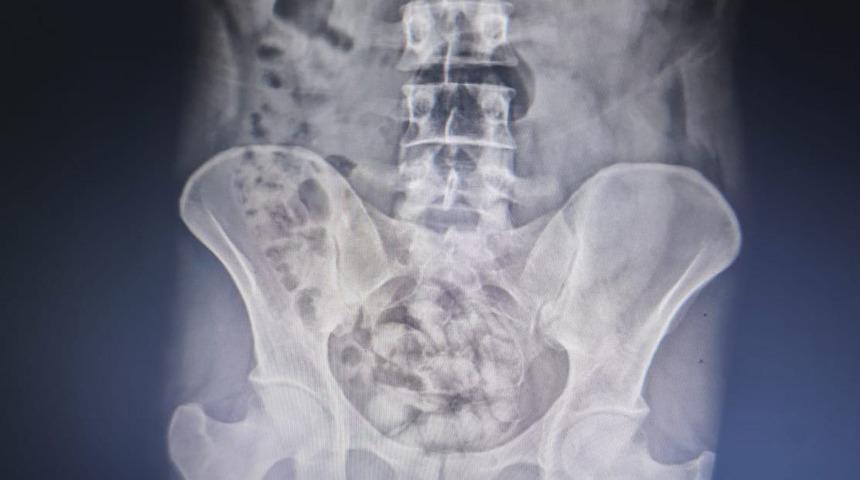

İran uyruklu S.Y.'nin üzerinde yapılan aramada, 23 gr metamfetamin ele geçirildi. Şüpheli davranışlarda bulunan S.Y., iç beden muayenesi için hastaneye götürüldü. Burada çekilen röntgen filminde midesinde 25 kapsül şeklinde paketlenmiş halde 351 gr gelen metamfetamin olduğu tespit edildi.

Hayatını riske atarak kuryelik yaptığı saptanan S.Y., midesindeki kapsül halindeki uyuşturucunun doğal çıkması için gözlem altına alındı.